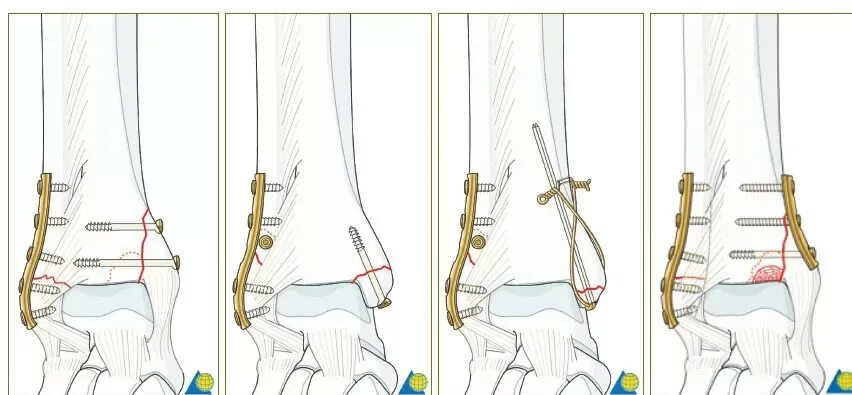

После остеосинтеза лодыжек